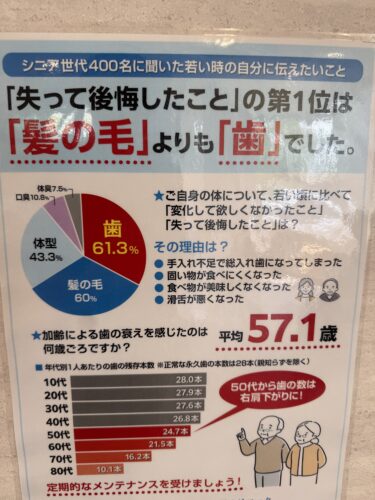

そして、毛よりも歯!だと言うこと。

皆さんも歯には十分気を付けて!